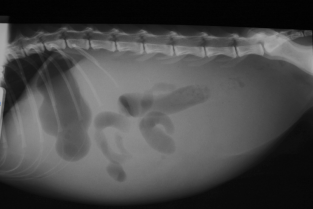

Le Professeur Jack-Yves Deschamps, chef de service des urgences d'Oniris, va nous présenter les différents mécanismes qui conduisent à la formation des épanchements abdominaux chez le chien et le chat, afin d'en déduire les causes qui les ont générés et d'envisager leur traitement.

Epanchements abdominaux chez le chien